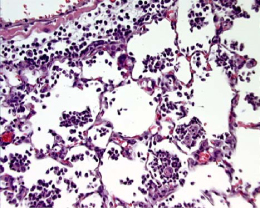

Figure 3. Intranasal LPSNote the predominance of neutrophilic intra-alveolar infiltrates with minimal deposition of hyaline membranes. |

Figure 3. Intranasal LPS